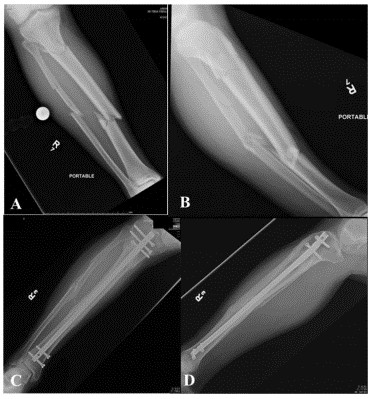

Сообщается о высоком проценте переломов нижней средней трети большеберцовой кости с переломами лодыжки. При использовании традиционной компьютерной томографии 43 % переломов средней и нижней трети большеберцовой кости сопровождались переломами голеностопного сустава, большинство из которых требовало хирургического лечения. Наиболее частым типом перелома был спиральный перелом нижней средней трети дистального отдела большеберцовой кости, связанный с переломом задней лодыжки с небольшим или несмещенным смещением (рис. 2). Из-за небольшого смещения связанного перелома лодыжки только 45 % повреждений можно обнаружить на обзорных рентгенограммах лодыжки. Таким образом, при наличии перелома нижней и средней части большеберцовой кости следует уделять особое внимание рутинному компьютерному сканированию голеностопного сустава (рис. 3).

Рисунок 3. Спиральный перелом AF средней и нижней трети левой большеберцовой кости (AB) на предоперационных рентгенограммах; (CD) предоперационная КТ, показывающая перелом задней лодыжки без смещения; (EF) демонстрирует плавное заживление перелома большеберцовой кости и лодыжки.